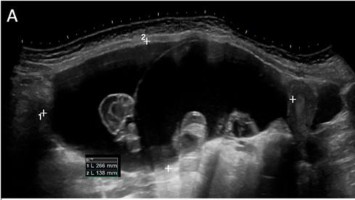

Ein 10-jähriges Mädchen in gutem Allgemeinzustand und altersentsprechender Entwicklung wurde aufgrund seit 4 Wochen bestehender und an Intensität zunehmender Unterbauchschmerzen zum Ausschluss eines entzündlichen Geschehens auf unsere Kinderstation aufgenommen. Mittels Bildgebung kamen die Ärzte der Ursache auf die Spur.

Akuter Harnverhalt in der Frühschwangerschaft